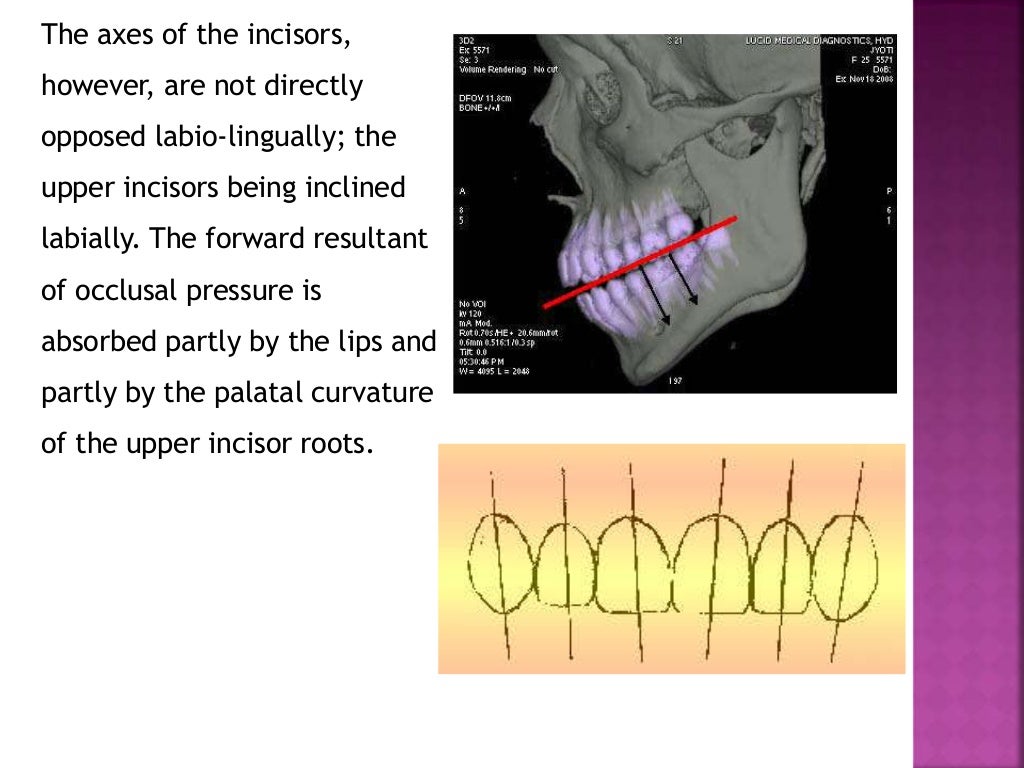

Forces of occlusion.ppt Occlusal Loading Force Inadequate distribution of occlusal forces can lead to various mechanical complications, including screw loosening, deformation, and fracture of the implant and. The biomechanical effects of occlusal loads on teeth during clenching and mastication and the transfer of occlusal forces. We clarified the effects of occlusal. We clarified the effects of occlusal loading force on occlusal contact in natural dentition by. Occlusal Loading Force.